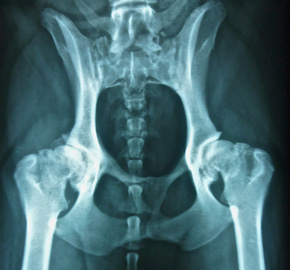

- Röntgen mit modernster digitaler Röntgenanlage

Offizielle HD, ED, und Rückenröntgen, Kontraströntgen